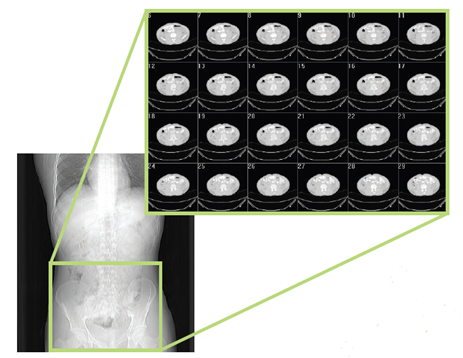

Infosys团队使用了一个老年骨质疏松患者椎骨的50张计算机断层扫描(CT)图像,这些CT扫描图像用于生成患者特定的3D CAD模型,该模型包含患者椎骨孔隙的确切形状和大小。在使用CAD模型进一步用FEA进行断裂风险分析之前,将CAD模型校准到实际尺寸大小。

设计仿真 | MSC Nastran助力Infosy公司精确评估骨折风险的图5

图:用于创建CAD模型的50张CT扫描图像中的24张